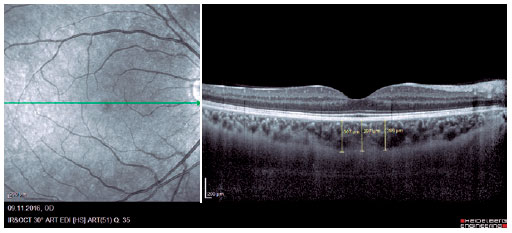

We retrospectively evaluated 32 obese patients with BMI of >30 kg/m2 who presented at the Internal Medicine Polyclinic due to obesity and who were also evaluated at the Ocular Diseases Polyclinic between January 2016 and June 2017 and 45 healthy control individuals. Eye IOP and OPA values of patients measured using Pascal DCT (Ziemer Group, Switzerland) and CT measured using enhanced depth imaging (centralized fovea for choroildal imaging) OCT (85,000 Hz OCT2 Next Generation SPECTRALIS OCT, Heidelberg Engineering) were assessed. These values were measured by the same physician and at the same time of the day. Only the most reliable measurements with scores 1 and 2 were included in the study. CT was manually measured by a single ophthalmologist based on the external boundary of retinal pigment epithelium and that of the choroidal vascular bed. It was measured three times at the subfoveal, nasal, and temporal regions at a distance of 500 µm from the macula, and the average of these three measurements was used for analyses (Figures 1-3). IR was assessed using the homeostasis model assessment-estimated IR (HOMA-IR) index(9), which was calculated as follows: HOMA-IR=[fasting plasma insulin (mIU/mL) × fasting plasma glucose (mmol/L)]/ 22.5(10). HOMA-IR index of 2.5 was set as the cutoff value(11). Patients with ocular tension and corneal disease, those with nonobesity systemic diseases, those who underwent eye surgery, and those who underwent interventions such as laser therapy and intravitreal injections were excluded from the study. This study was approved by the Ethics Committee of the Adiyaman University (#2017/7-19).